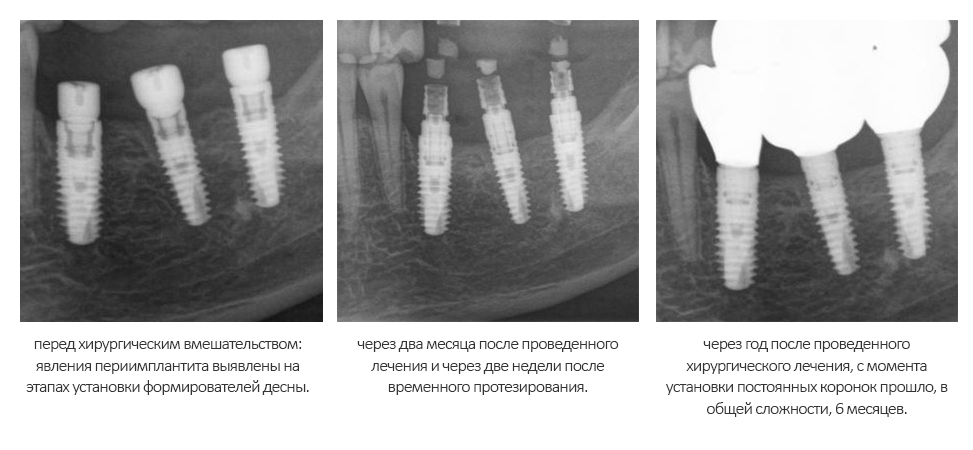

Помимо этого, один из этапов лечения периимплантита предполагает «превращение» субгингивального имплантата в трансгингивальный (подробности здесь>>). Описанную в статье методику можно считать успешной —  она, пусть и не восстанавливает уровень костной ткани вокруг имплантатов, но помогает избежать развития заболевания и потери имплантатов вообще:

То есть, если часть имплантата находится не в кости — в этом нет ничего страшного и предосудительного. Так почему нужно переживать из-за того, что имплантат вышел  за пределы костной ткани, пусть и в сторону верхнечелюстной пазухи?